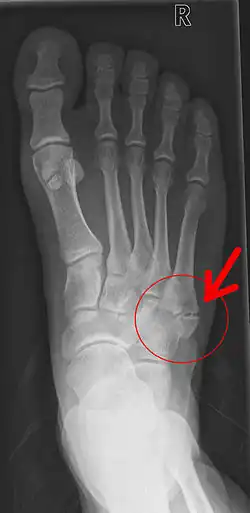

Dependiendo del hueso afectado las fracturas del pie se clasifican en los siguientes tipos:

- Fractura de metatarsiano.